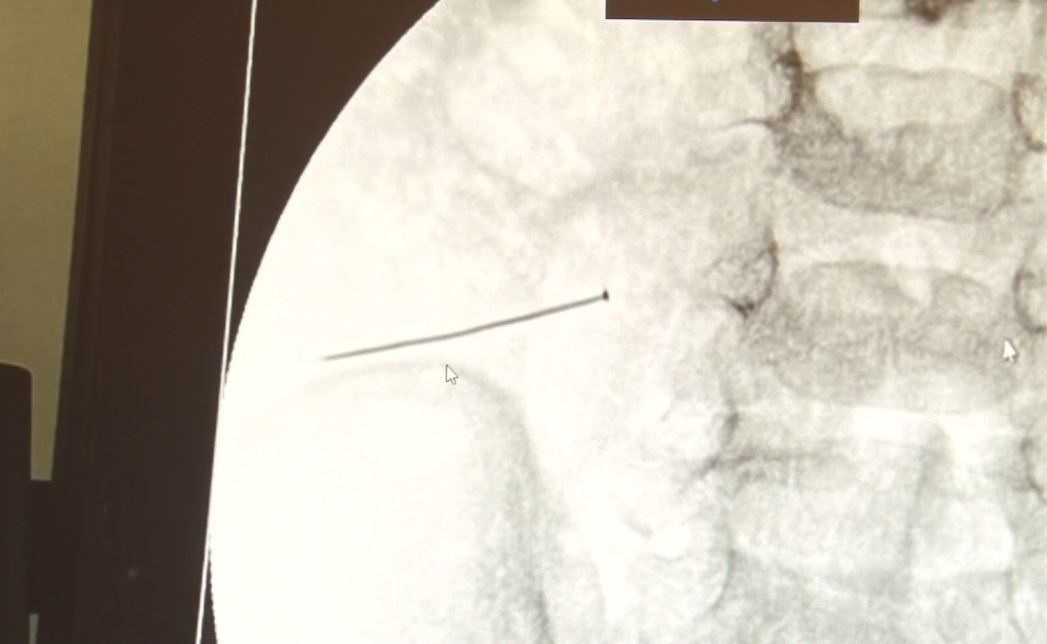

Öte yandan, yaklaşık 3 santimlik toplu iğne filme yansıyan görüntüsüyle gözler önüne serildi.

İstanbul’da 2 yaşındaki çocuk iddiaya göre toplu iğne yuttu sonrasında adeta karın ağrısıyla yerinde duramaz hale geldi. Babaanne, küçük çocuğun şikayetleri üzerine Şehit Prof. Dr. İlhan Varank Sancaktepe Eğitim ve Araştırma Hastanesi’ne götürdü. Burada yapılan tetkiklerde 2 yaşındaki çocuğun ince bağırsağında yaklaşık 3 santimlik toplu iğne olduğu ve bağırsağı deldiği belirlendi. Görüntülemeler sonrası 30 Ekim akşamı Çocuk Cerrahisi Kliniği Eğitim ve İdari Sorumlusu Doç. Dr. Sefa Sağ ve ekibi hemen ameliyata girdi. Başarılı operasyonla iğne olduğu noktadan alınırken aile de rahat bir nefes aldı. Doç. Dr. Sağ ise taburcu edilen hastasının durumuna ilişkin bilgi verirken yabancı cisim yutmalarına karşı ailelere önemli uyarılarda bulundu.

Çocuklarda yabancı cisim yutulmasına yönelik konuşan ve hastasına ilişkin bilgi veren Doç. Dr. Sefa Sağ, "Soluk borusuna kaçması durumunda çocuğun Allah göstermesin ölümüyle veya ömür boyunca yatağa bağımlı kalmasıyla neticelenebilecek sonuçlar doğurabiliyor. Yutulması durumunda da gastrointestinal sistemin herhangi bir yerine takılmadığı müddetçe ekseriyâ yabancı cisimlerin dışarıya çıkmasını bekliyoruz. Yabancı cisim yutulmasını 2 grupta inceleyebiliriz. Sıvı ve katı cisimler olarak sıvı; evde kullanılan kimyasal temizlik malzemelerinin yutulması çok ciddi problemler oluşturabilmekte. Ağızda, yemek borusunda ve midede yanıklar meydana getirebilmekte. Uzun dönemde çocukların hayat kalitesini oldukça etkileyen sonuçlar doğurabilmekte. Katı cisimlerden de ekseriyâ kendiliğinden çıkmasını bekleriz ancak böyle delici, kesici aletlerin yutulmasında ise herhangi bir bağırsağın veya gastrointestinal sistemin bir parçasında delinmeler meydana getirebiliyor. Bu çocuğumuzda da aynen böyle bir hadise meydana gelmişti. Sanırım 1 gün önce ailenin yuttuğunu tahmin ettiği bir yabancı cisim; toplu iğne. Ertesi gün bağırsakta delinmeyle sonuçlanmış ve çocukta da ciddi semptomlar meydana getirmişti. Bu şekilde hasta bize başvurdu. Tetkikler sonucunda yabancı cismi tespit ettik, semptomları ve bulgularına göre de çocuğu ameliyata aldık. Yaklaşık 3 santim boyunda bir toplu iğnenin ince bağırsağı deldiğini, ince bağırsaktaki içeriğin de karın içerisine dolduğunu gördük. Ameliyatı başarılı bir şekilde tamamladık, yaklaşık 1 saat süren bir ameliyattı" dedi.